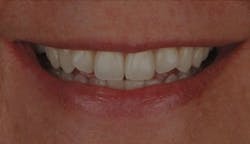

Figure 10: Patient B presented for esthetic concerns about the two centrals. I always make a photo with the lips framing the smile; this comes into play after the dentistry has been performed (figure 12).

Figure 12: Patient B after the central incisors were restored: Often, the patient’s lip line will rise higher following an esthetic improvement. Showing potential patients this type of photograph—with lips—makes a bigger impact than a retracted photo.